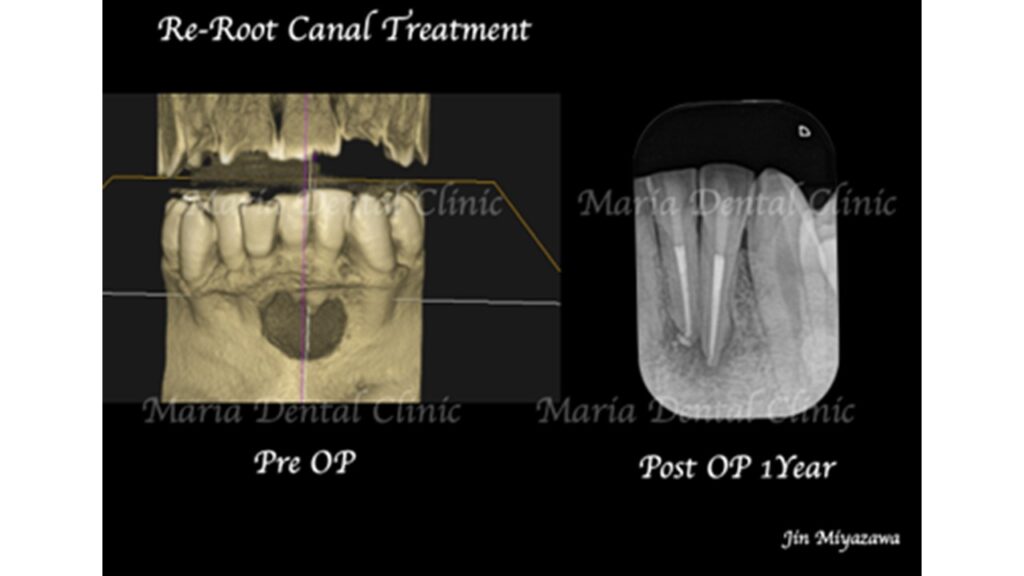

患者様は数年前にかかりつけ医で根管治療を行い、セラミックを装着されたとのことです。しかし治療直後より右下の歯茎の腫れをおかしいと思い、かかりつけ医に相談したところ経過観察を促され、そのまま放置していたとのことでした。今回、歯ぐきの腫れがひどくなったことから、再度かかりつけ医に相談したところ抜歯を宣告されたとのことです。

術前の写真を確認すると根の先端から広がる病変の影は歯の股の部分まで大きくなっていることが確認できます(術前写真②)